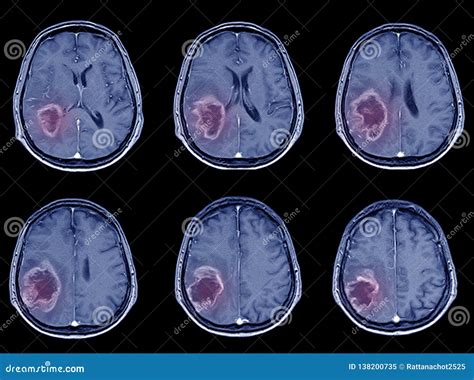

Early Signs of Ischemic Stroke on a CT Scan

In the early stages of an ischemic stroke , the CT scan might not show a lot of obvious changes. However, there are some subtle signs that experienced radiologists can spot. They look for the following signs:

Later Signs of Ischemic Stroke on a CT Scan

As time passes, the changes on the CT scan become more apparent. The following signs are usually visible later:

• Hypodensity: Areas of the brain that are damaged due to the lack of blood flow will start to appear darker on the CT scan. This is called hypodensity. It indicates that the brain tissue is dying.

• Mass Effect: As the brain swells, it can push on other structures, causing a mass effect.

• Infarct: This is a term for the area of dead tissue caused by the stroke. It can be seen as a clearly defined dark area on the scan.

Differentiating Ischemic vs. Hemorrhagic Stroke

One of the main goals of the CT scan is to differentiate between an ischemic stroke and a hemorrhagic stroke. A hemorrhagic stroke involves bleeding in the brain. On a CT scan, blood appears bright white. So, if the scan shows any bright white areas, it’s a sign of bleeding. If there’s no bleeding and the scan looks relatively normal (or shows the signs of ischemic stroke ), then it’s most likely an ischemic stroke . This distinction is super important because the treatments for each type of stroke are different.